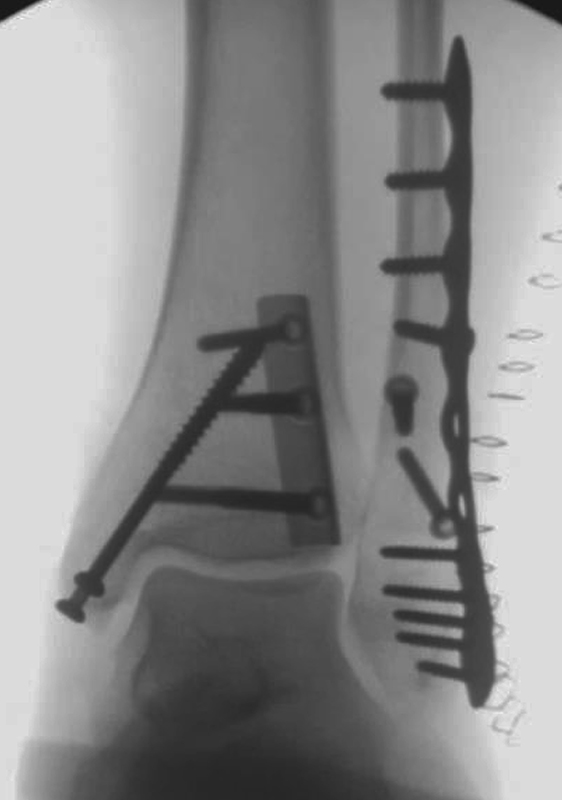

Die Versorgung von AO 44-B Frakturen erfolgt über einen längsverlaufenden lateralen Zugang. In der Regel gelingt eine suffiziente Stabilisierung mittels interfragmentärer Zugschraube (bei langem Frakturverlauf ggf. 2 Zugschrauben) und einer zusätzlichen Neutralisationsplatte (Abbildung 9 & 10).

Bei multifragmentären Frakturen (AO 44-B2.3) oder bei schlechter Knochenqualität sollte die Versorgung mittels winkelstabiler Plattenosteosynthese erwogen werden (Abbildung 11 & 12).

Frakturen vom Typ AO 44-C werden in der Regel mittels interfragmentärer Zugschraube und Neutralisations-Plattenosteosynthese versorgt. Die Versorgung von Frakturen mit metaphysärer Trümmerzone (AO 44-C2) ist mitunter anspruchsvoll. Entscheidend ist die Wiederherstellung der korrekten Länge und Rotation der Fibula. Die Verwendung von winkelstabilen Implantaten bietet hier eine höhere Stabilität. Bei Typ C Verletzungen liegt definitionsgemäß eine Syndesmoseninsuffizienz vor, die entsprechend versorgt wird (siehe Abschnitt Syndesmoseninsuffizienz). Bei hohen Fibulafrakturen (AO 44-C3, Maisonneuve-Frakturen) steht die Versorgung der Syndesmoseninstabilität im Vordergrund. Eine zusätzliche Versorgung der proximalen Fibulafraktur ist nicht erforderlich.

Gardner et al. konnten beispielsweise zeigen, dass die offene anatomische Reposition der Tibiahinterkante der Stabilisierung mittels Stellschraube überlegen war und gleichzeitig mit einer geringeren Rate an postoperativen Fehlstellungen der Fibula in der CT-Kontrolle einherging 2728. Aus Sicht der Autoren ist prinzipiell die Stabilisierung über eine direkte Reposition indiziert, wenn die Größe des Fragmentes dies erlaubt. Bei gleichzeitigem Vorliegen einer Fraktur des lateralen und/oder medialen Malleolus sollte zunächst die Versorgung der des Tibiahinterkantenfragments erfolgen. Dies erlaubt die radiologische Kontrolle der Reposition und Osteosynthese-Lage, welche durch eine zuvor aufgebrachte Fibula-Platte häufig erschwert ist 29. Dafür werden die Patienten in Seitenlage gelagert. Dies erlaubt die direkte Versorgung der posterioren Malleolusfraktur über einen posterolateralen Zugang 30. Das sehr kräftige Periost wird im Frakturverlauf inzidiert und aus den Frakturspalt entfernt, so kann eine anatomische Reposition erfolgen. Entsprechend der Fragmentgröße erfolgt entweder die Versorgung mittels Drittelrohrplatte in Antiglide-Technik oder eine Zugschraubenosteosynthese. Die Versorgung der Fibula-Fraktur gelingt über den gleichen Zugang. Zur Versorgung des medialen Malleolus wird der Patient auf den Rücken umgelagert. Dies kann bei entsprechender Vorbereitung ohne erneutes steriles Abdecken erfolgen. Durch dieses Vorgehen konnte im eigenen Kollektiv die Notwendigkeit einer Stabilisierung der Syndesmose mit Stellschraube/Tight Rope deutlich reduziert werden.

Liegt eine Syndesmosen-Insuffizienz vor (Abbildung 18), so erfolgt nach der Osteosynthese aller Frakturen im ersten Schritt die Reposition der Fibula in die Incisura fibularis der Tibia mittels Repositionszange. Danach sollte geprüft werden, ob die Dorsalextension im OSG noch uneingeschränkt möglich ist. Falls vorhanden, ist es hilfreich die korrekte Reposition mittels intraoperativen CT zu kontrollieren. Die Durchführung eines intraoperativen 3D Scans konnte nach zufriedenstellenden Ergebnissen in der konventionellen 2D Bildgebung bereits intraoperativ in 20-40% ein korrekturbedürftiges Ergebnis zeigen 3132. Anschließend erfolgt das Einbringen einer Stellschraube oder eines Tight Ropes (Abbildung 19). Dabei sollte darauf geachtet werden, dass die Bohrung knapp proximal des distalen Tibio-Fibular-Gelenkes angelegt wird. Die Bohrung sollte in 30° von posterior nach anterior und parallel zur Gelenklinie des OSG gerichtet sein. Beim Einbringen der Schraube ist darauf zu achten, die Fibula nicht an die Tibia zu komprimieren. Postoperativ empfehlen wir die Durchführung einer CT-Untersuchung des verletzten und des unverletzten Sprunggelenkes. Nur so ist aus unserer Sicht die Reposition der Fibula sicher zu beurteilen.